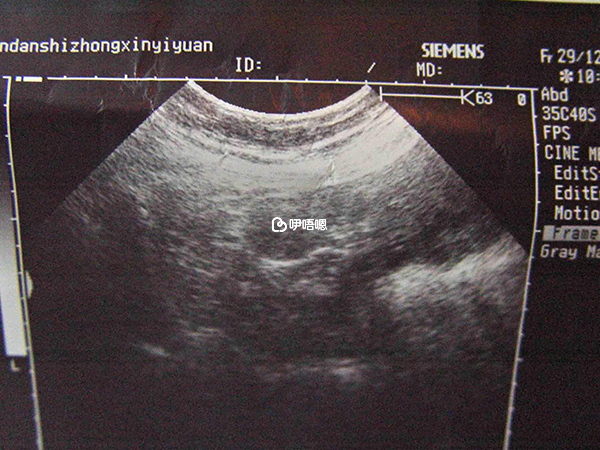

女性懷孕後,據說可以通過B超單子看生男生女,通常在孕婦懷孕三個月以後,男胎和女胎生殖器官開始分化,在B超檢查時下半身影像並不一樣,從超聲影象上來看,男孩和女孩最明顯的區別,就是生殖器官不一樣,下面這張B超影象,代表懷的是男孩。

圖片可以看到有突出的東西,也就是小雞雞的圖片很清晰,這是男胎最明顯的標誌,如果是女孩的話,可能看不到突出的一些東西,反而會看到明顯的三條白線,這是女寶寶非常明顯的標誌,這是男孩和女孩的區別。

1、寶媽分享懷男孩小雞b超單圖片